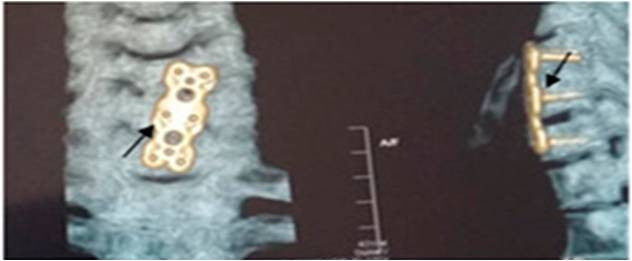

Պարանոցային հատվածի առաջնային ֆիքսացիան կատարվում է այս հատվածի միջողային աճառների ճողվածքների բաց եղանակով հեռացման դեպքում, կամ վնասվածքների ժամանակ: Վիրահատության

ժամանակ երկու ողի մարմինները ֆիքսվում են տիտանե թիթեղով, ինչպես պատկերված է նկարում:

Պարանոցային հետին ֆիքսացիան կատարվում է վնասվածքների, ուռուցքների դեպքում կամ էլ կապանահոդային հյուսվածքի գերաճի հետևանքով առաջացած ողնուղեղի կոմպրեսիայի և միելոպաթիայի կապակցությամբ կատարված լամինէկտոմիայից հետո: Ահա այպիսի տեսք ունի կռանիոցերվիկալ ֆիքսացիան, որը համարվում է պարանոցային հետին ֆիքսացիայի տեսակներից մեկը: